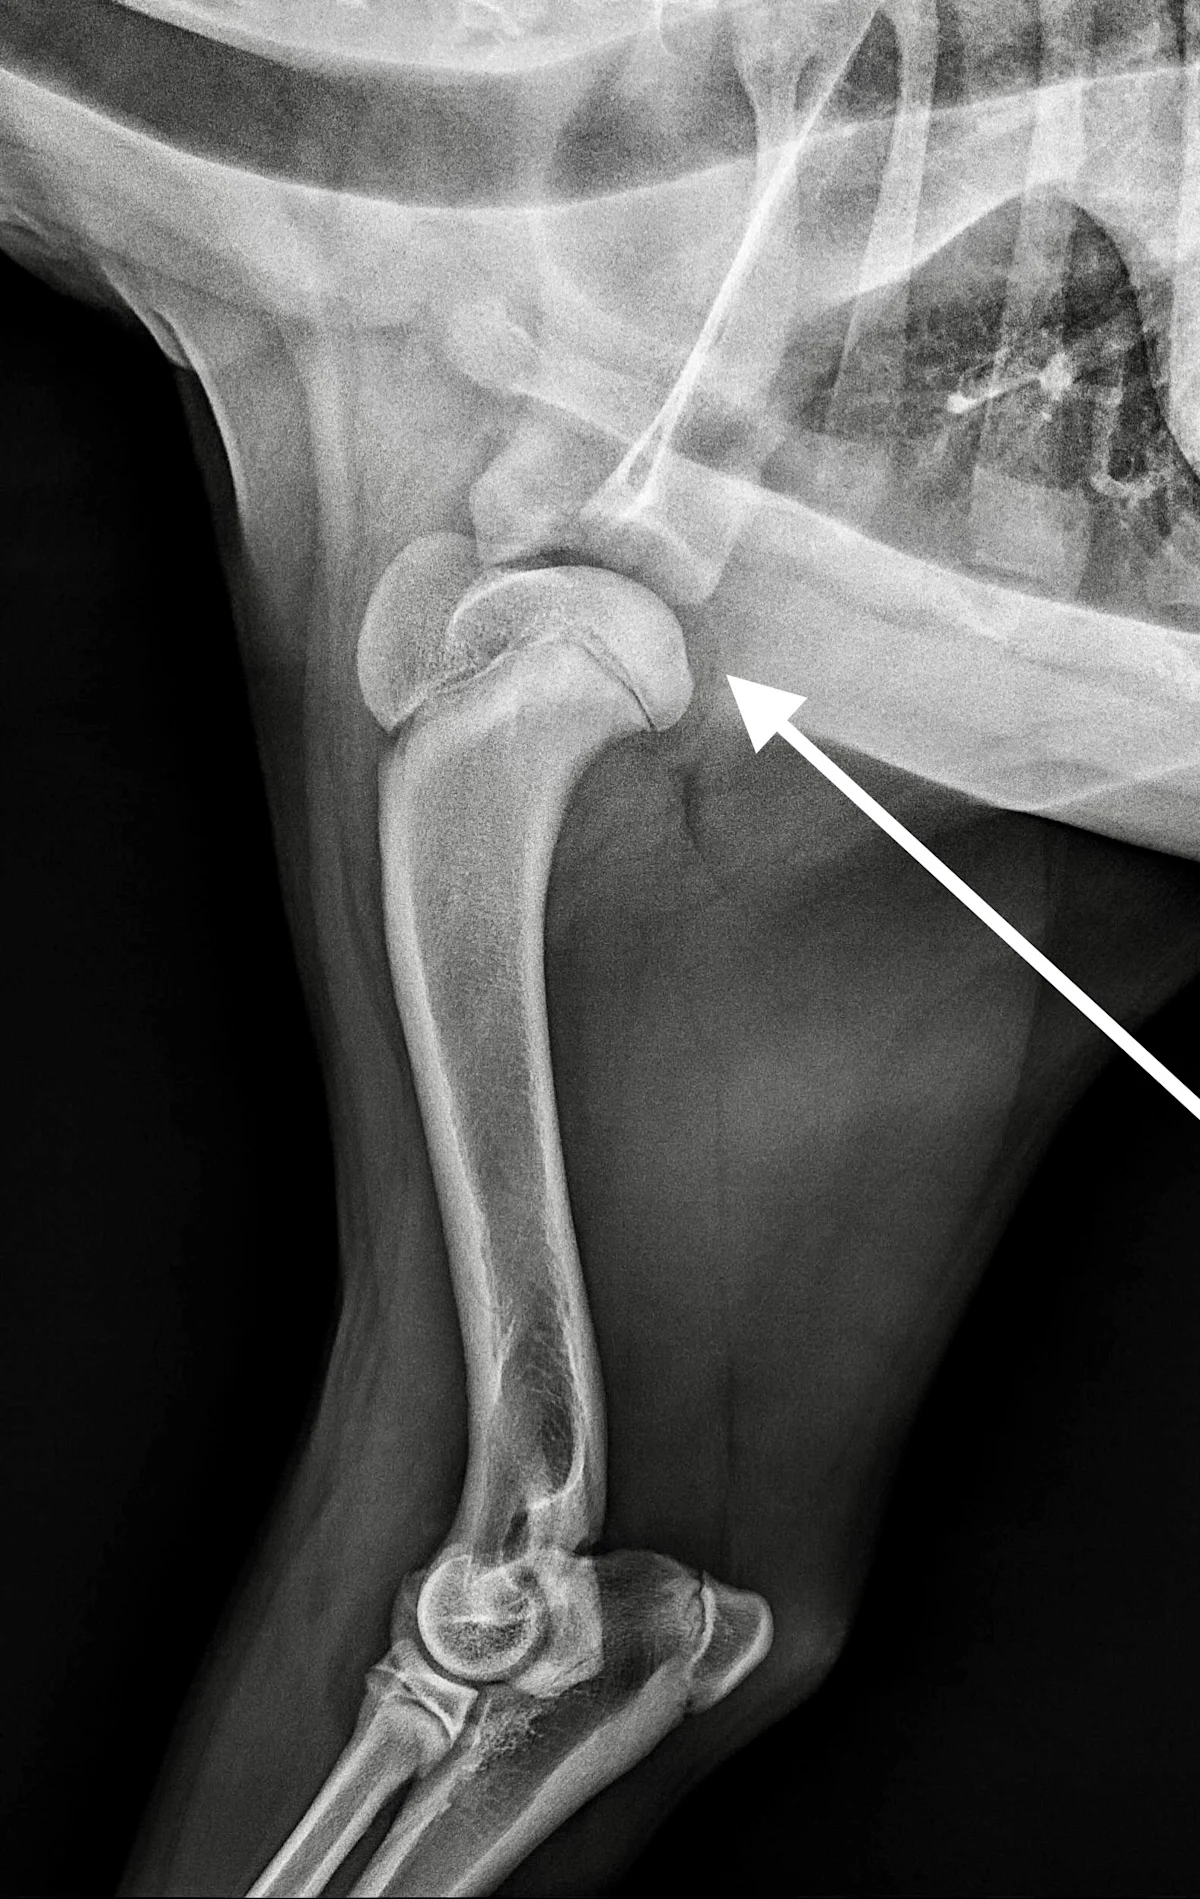

FIGURE 1 Lateral radiograph of the shoulder revealing the typical flattening of the caudal humeral head (arrow)